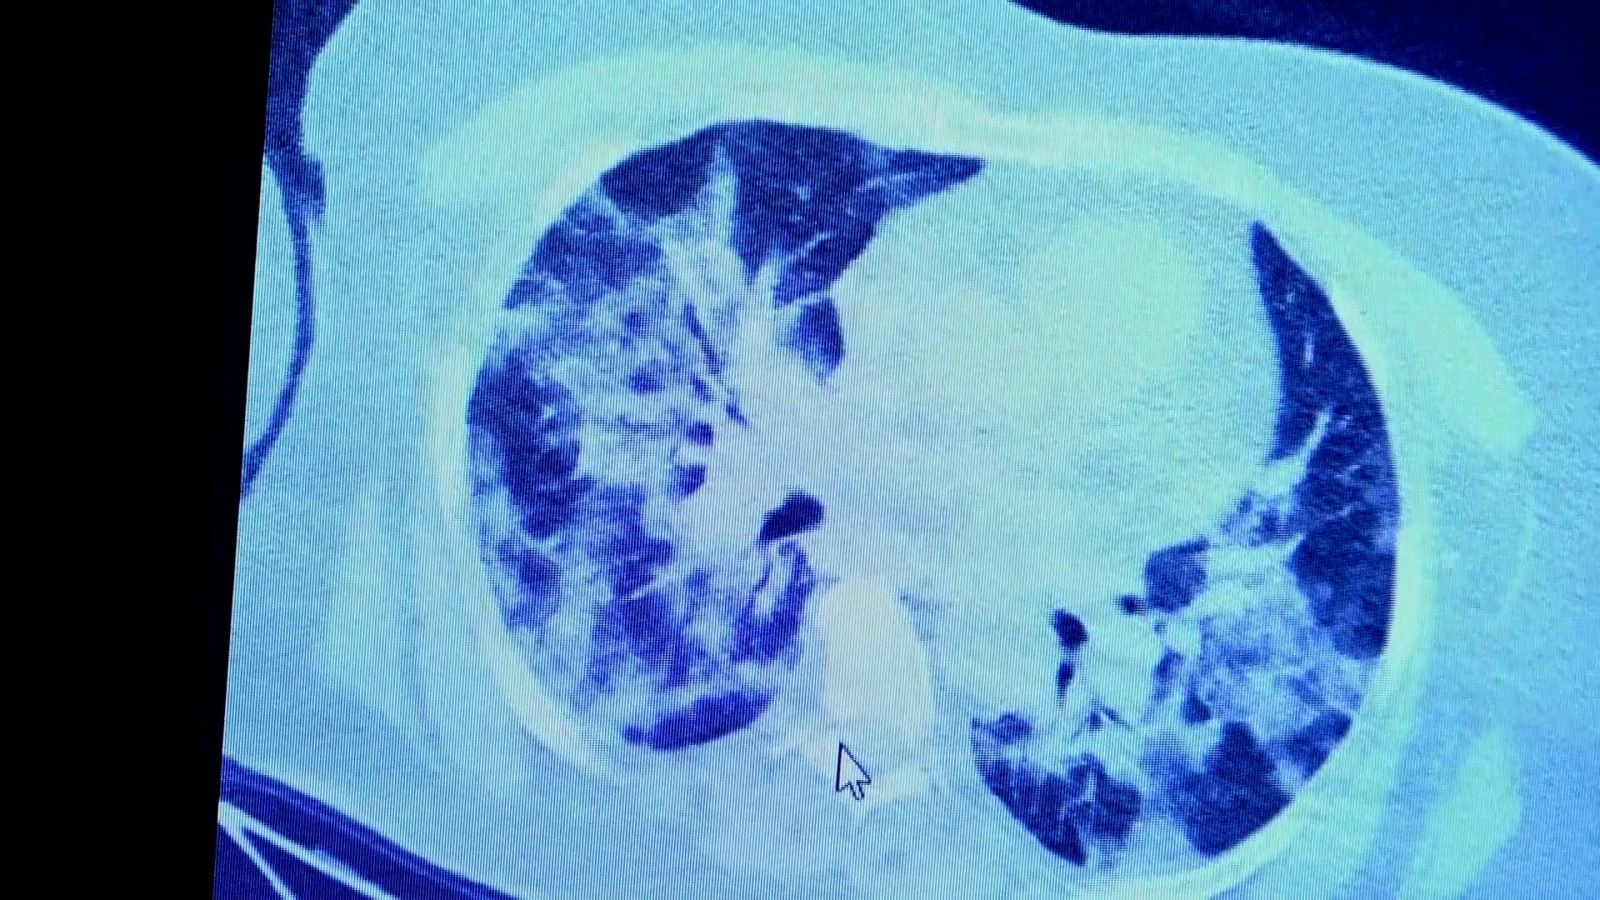

VM Medical Park Samsun Hastanesi’nde görev yapan Göğüs Hastalıkları Kliniği’nden Prof. Dr. Şevket Özkaya da bir hafta ilaç kullanmayan bir pozitif hastanın akciğer tomografisini inceledi. Hasta pozitif haldeyken ilk akciğer tomografisine bakıldı. Tomografide akciğerlerdeki tutulmanın az olduğu gözlemlendi. Akabinde aynı hastanın verilen ilaçları kullanmamış ve 1 hafta boyunca tedaviye uymamış haldeki akciğer tomografisine bakıldı. Sonuç ise ilaç kullanımının önemini ortaya çıkardı. Hastanın akciğer tomografisinde yaygın buzlu camların ve hava yollarının hava yerine ciddi şekilde sıvı ile dolduğu gözlemlendi.

Akciğer tomografisinde oluşan değişim ile ilgili bilgi veren Prof. Dr. Şevket Özkaya, "Ekranda 55 yaşında bir kadın hastamızın filmini görüyorsunuz. Bu kadın hastamız acil servisimize ateş şikâyetiyle geldi ve korona virüsünden şüphe ettik. Testini yaptığımızda ise testin sonucu pozitif geldi. Tomografi çektiğimiz zaman akciğerlerinde henüz ciddi bir tutulum görünmezken hastamız 55 yaşında olduğu için her an ilerleyebilir korkusuyla Sağlık Bakanlığımızın önerdiği ilaçları ve reçeteyi hastanemizden kendisine verdik. Hasta kendini evde karantinaya aldı fakat sonradan öğrendik ki tereddüt ettiği için ilaçlarını kullanmayarak kendini evde tedavisiz bırakmış. Yaklaşık bir hafta sonra aynı hasta acil servisimize bu sefer solunum yetmezliği şikâyetiyle geldi. Solunum yetmezliği gelişince hastanın akciğer tomografisinde ‘buzlu cam’ dediğimiz ve daha ileri konsolide alanların oluştuğunu gördük. Yaygın akciğer harabiyeti dediğimiz bir tablo oluşmuştu. Bu durumda hastada solunum yetmezliği olduğu için yoğun bakıma almak zorunda kaldık" dedi.

Hastalığa yakalandıktan sonra mutlaka doktora görünmek gerektiğini ifade eden Prof. Dr. Özkaya, "Mart, Nisan ve Mayıs aylarında yani pandeminin en yüksek olduğu dönemlerde, her evde bir pozitif vak'a gelince biz şaşırıyorduk fakat şimdi ailedeki herkes pozitif oluyor. Bu yüzden ailenizi ve toplumu seviyorsanız kurallara uyun ve bakanlığımızın önerdiği tedavilerden kaçınmayın diyoruz. Çünkü virüs enfekte ettikten bir süre sonra akciğerlerde yaygın buzlu camlara ve konsolidasyona neden oluyor. Eğer zamanında tedaviye başlanmazsa, bu durum solunum yetmezliğine kadar gidip maalesef hastanın kaybına yol açıyor. Bu yüzden mümkün olduğunca bilinçli ve kurallara uygun şekilde davranmamız gerekiyor" şeklinde konuştu.